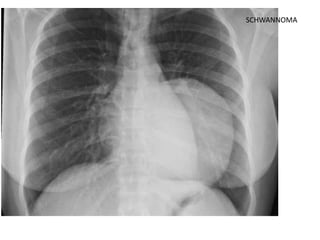

SCHWANNOMA

On conventional radiographs look for:

• Cervicothoracic Sign

• Widening of the paravertebral stripes

• The anterior mediastinum stops at the level of

the superior clavicle.

Therefore, when a mass extends above the

superior clavicle, it is located either in the neck or

in the posterior mediastinum.

When lung tissue comes between the mass and

the neck, the mass is probably in the posterior

mediastinum.

This is known as the Cervicothoracic Sign.